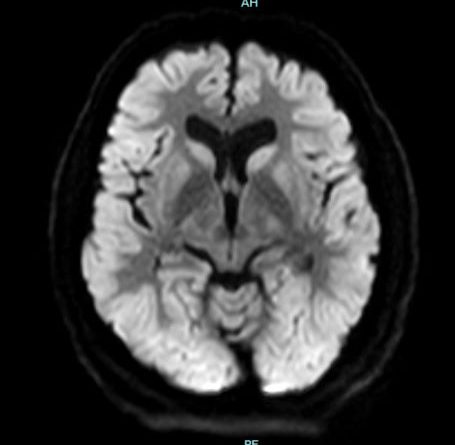

66 yaş, E

Kardiak arrest, 10 dk CPR öyküsü

15.03.2025

24.03.2025 takip

Hipoksik iskemik ensefalopati (orta derecede)

hipoksik iskemik ensefalopati subakut evre

Hipoksik İskemik Ensefalopati

Diffüz Anokaik Ensefalopati

Diffuz hipoksik iskemik ensefalopati